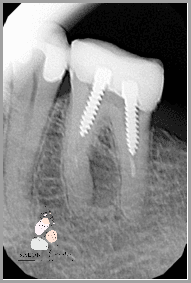

Jeśli masz ból zęba po leczeniu kanałowym, należy skontaktować się z lekarzem stomatologiem w celu ustalenia przyczyny. Lekarz może zlecić zdjęcie RTG, aby zobaczyć, czy ząb jest w dobrym stanie. W przypadku wykrycia problemu lekarz może zalecić dodatkowe leczenie, aby wyeliminować ból. Możliwe jest również zastosowanie znieczulenia lub innych metod łagodzenia bólu.